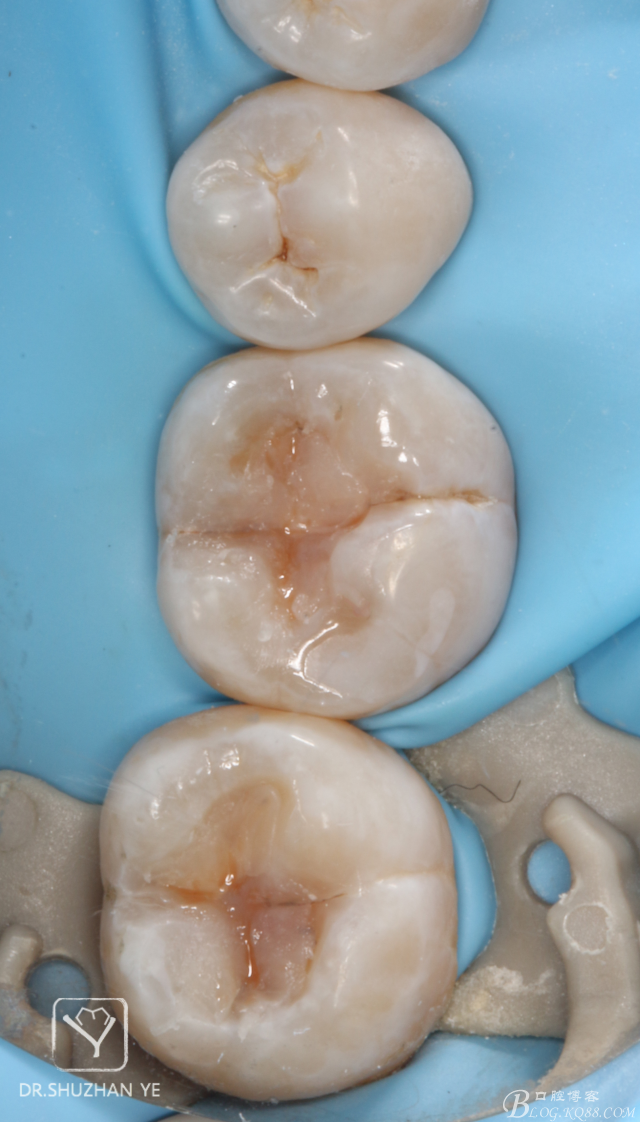

7、牙本質(zhì)層充填完成,窩溝染色

20151205082632_80662.jpg

8、牙釉質(zhì)層堆塑,印章按壓完成,涂布氧阻滯劑光照固化

20151205082641_42453.jpg